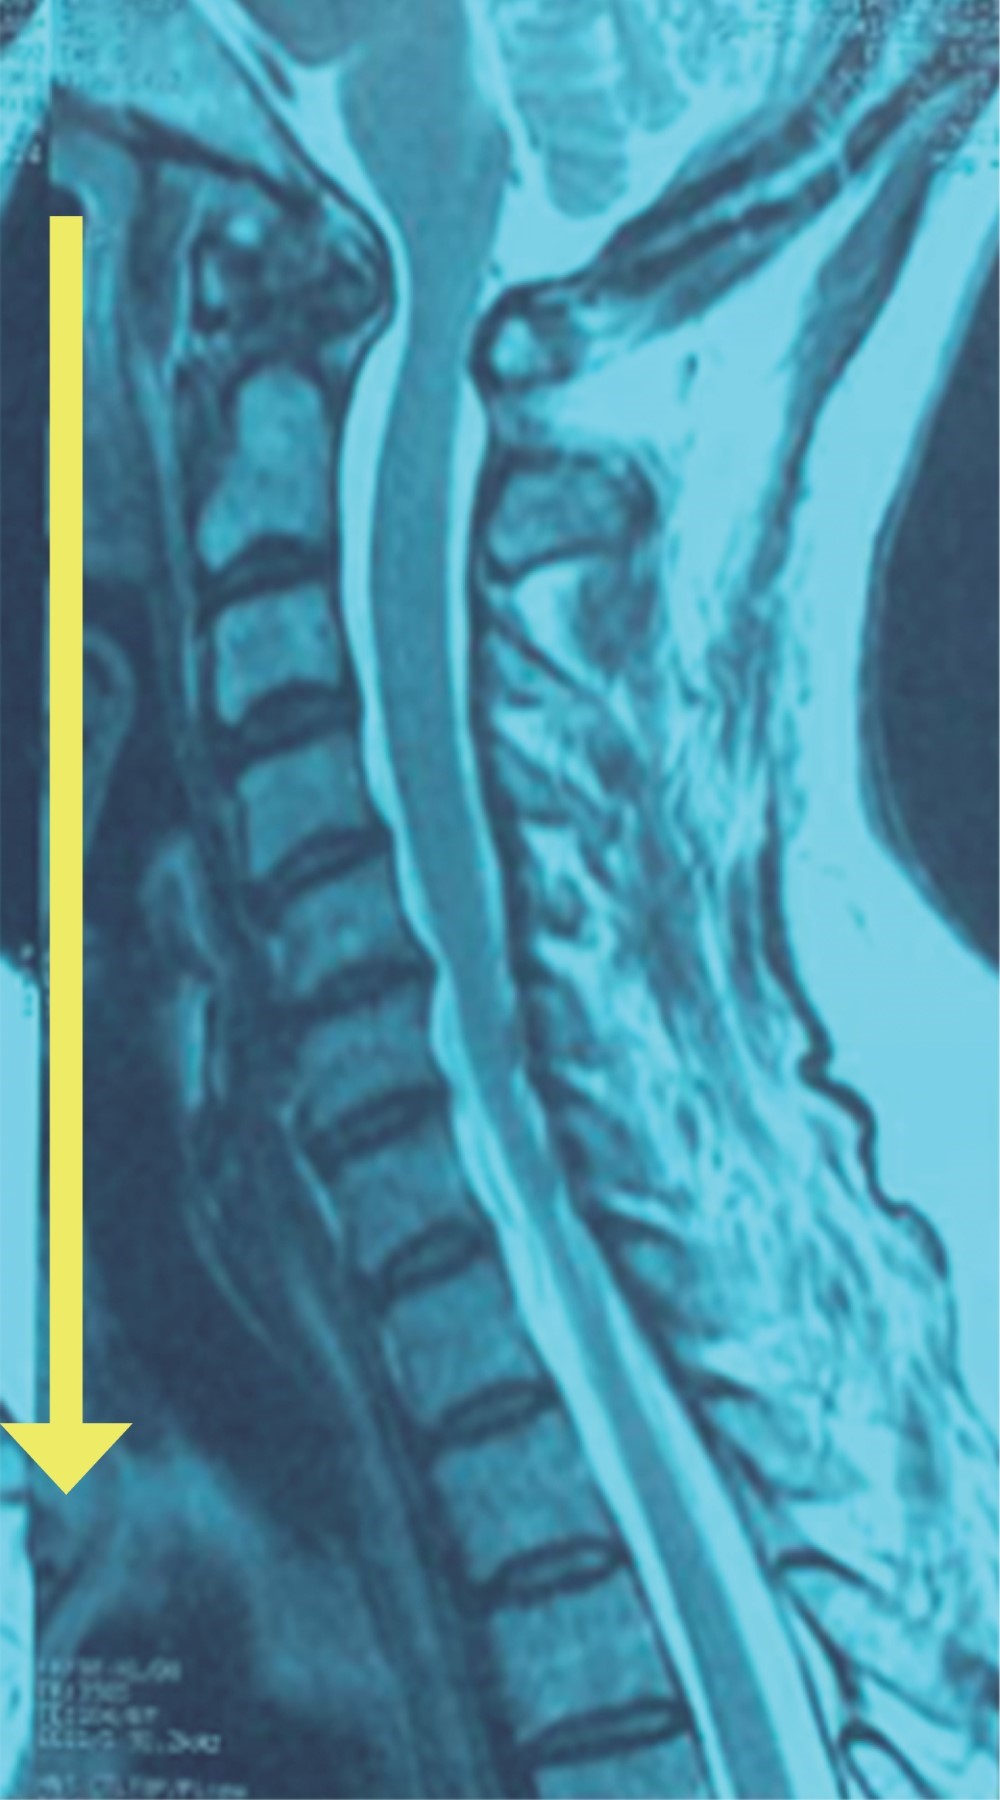

A tres pacientes se les realizó resonancia magnética de columna cervical simple (Figuras 3, 4 y 5), los días de realización variaron debido a que dos de ellos se encontraban en institución pública y la accesibilidad a la resonancia magnética no pudo ser inmediata. En los tres se presentó una hiperintensidad con forma de flecha, la cual se localizaba en el espacio prevertebral y que llegaba hasta C1-C2 (Figuras 3, 4 y 5). La hiperintensidad era isointensa respecto al líquido cefalorraquídeo que se observaba en el conducto raquídeo. En uno de los casos se pudo documentar un trayecto fistuloso, pero no fue constante en ninguno.

Como se puede observar en las imágenes previas, en la secuencia T2 en un corte sagital puede observarse una hiperintensidad en el espacio intervertebral que nos indica que en ese sitio se encuentra impregnado de líquido cefalorraquídeo, ya que la hiperintensidad es igual a la observada en el conducto raquídeo.

Como se puede observar en las imágenes previas, en la secuencia T2 en un corte sagital puede observarse una hiperintensidad en el espacio prevertebral que nos indica que en ese sitio se encuentra impregnado de líquido cefalorraquídeo, ya que la hiperintensidad es igual a la observada en el conducto raquídeo.

El signo de la flecha puede ser un indicador muy fiable para el diagnóstico y seguimiento de las fístulas de LCR originadas en la discectomía de la columna cervical realizada vía anterior (Figuras 6 y 7). La misma se visualiza mejor en la secuencia T2 en el corte sagital de una resonancia magnética simple de columna cervical. Su identificación puede ayudarnos a tomar decisiones sobre esta pequeña gran complicación.